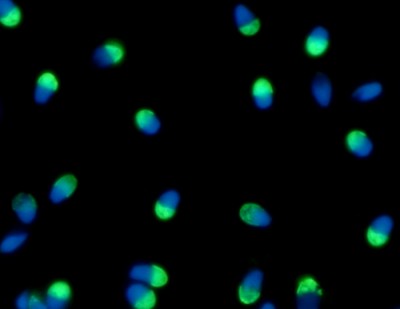

El grupo de trabajo de la doctora Vanesa Rawe fue de los primeros en Argentina en implementar una novedosa tecnología llamada “Columnas de Anexinas V” que selecciona espermatozoides de buena calidad desde una muestra en que la que abundan espermatozoides con ADN fragmentado, los que no logran fecundar un óvulo.

Su uso permite mejorar muestras de espermatozoides afectadas ya que se enriquece la muestra en células sanas y como consecuencia la probabilidad de incrementar las tasas de éxito de la fertilización in vitro”, señala la doctora Rawe, especialista en reproducción de la UBA y posdoctorada en la Universidad de Medicina de Pittsburgh, en Estados Unidos. Y explica: “La técnica consiste en incubar proteínas anexina V con la muestra espermática afectada.